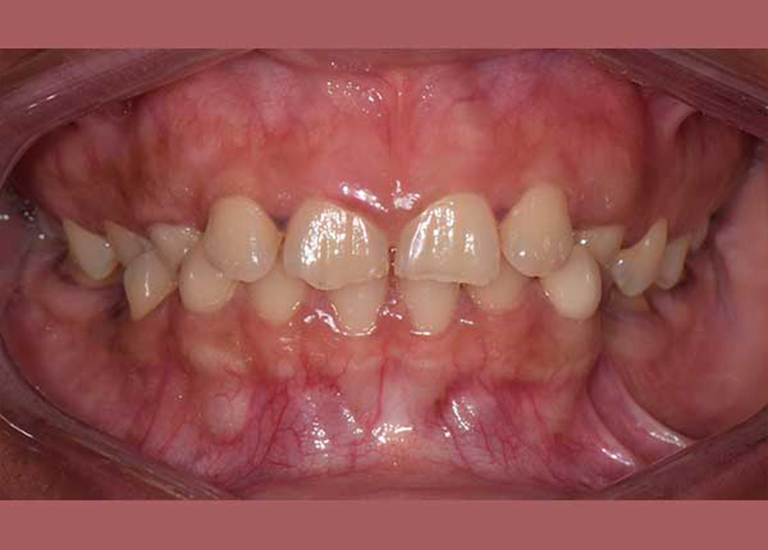

BEFORE

Since she was a child, this woman has suffered from an impacted upper canine -they didn’t erupt in their normal place- and her milky canines were still in her mouth.

She was complaining about the emergence of her lower canines inward, which causes her big problems in eating and speech, and she wasn’t able to smile comfortably, she even refused To photograph her smile at first.

By examining the case and taking X-rays, I observed the upper canines in her mouth, and an embedded lower premolar was observed too on the left side, I started the treat the case, but because of the old age of this lady, the upper canines and the left lower premolar did not erupt on their own after we extracted the temporary canines, and she had to pull them out by braces. As for the lower jaw; The canines were pulled back in place and the embedded premolar was orthodontically pulled.